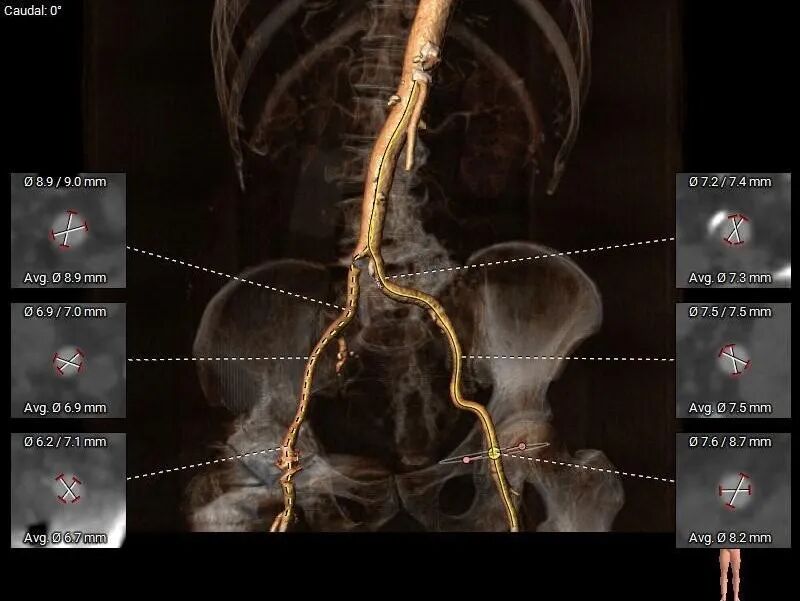

股-髂动脉走行稍迂曲,内径可,右侧股动脉穿刺点偏下位置有钙化块分布,腹主-髂总大量附壁钙化

•股-髂动脉走行稍迂曲,内径可,右侧股动脉穿刺点偏下位置有钙化块分布,腹主-髂总大量附壁钙化,

股-髂动脉走行可,内径可,几乎无钙化分布。